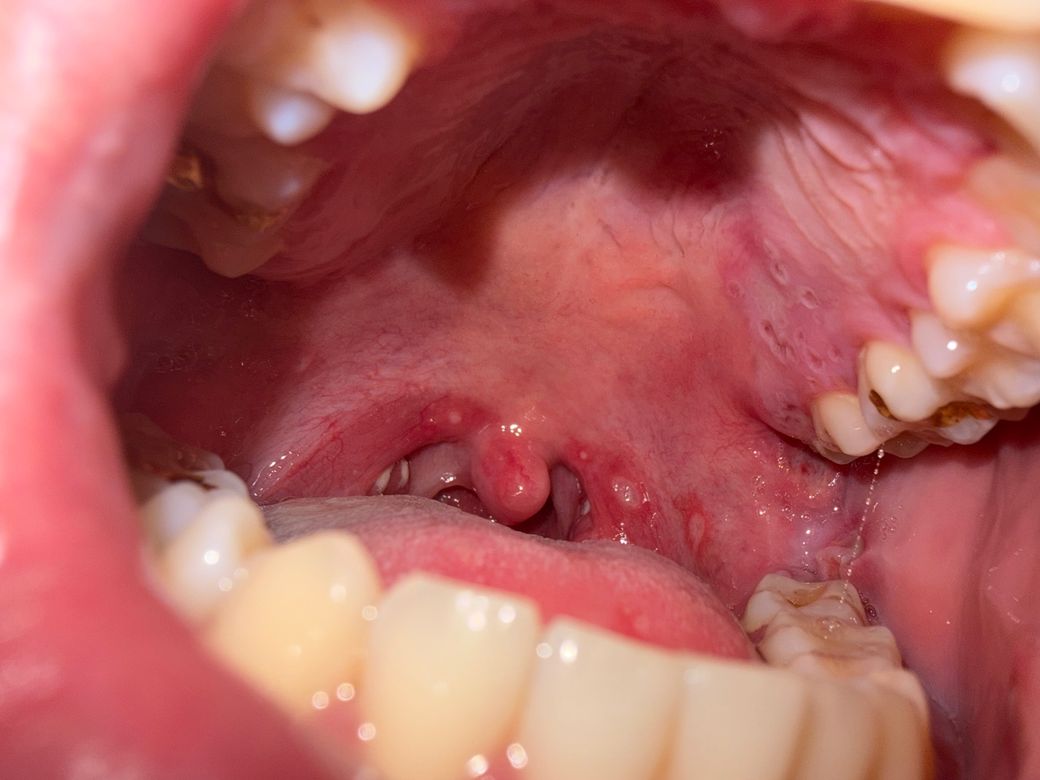

지금 편도염 및 구내염으로 치료중인데 입천장이 너무 아파서 사진찍어보니 사진처럼 패여있습니다

• 사진상 입천장(연구개 부위)에 경계가 비교적 분명한 얕은 궤양이 보이고, 주변 점막은 충혈되어 있습니다. 현재 편도염과 함께 발생했다는 점을 고려하면, 바이러스성 구내염(특히 헤르페스성 인두구내염) 가능성이 더 높아 보입니다. 이런 경우 통증이 매우 심하고 음식 섭취가 어려운 경우가 흔합니다.

오라페인큐겔(국소 마취·소염 성분)은 입천장 궤양 부위에 소량 도포해도 됩니다. 다만 도포 직후 음식 섭취는 점막 손상 위험이 있어 30분 정도 피하는 것이 안전합니다. 통증이 매우 심하면 경구 진통소염제 병용이 필요할 수 있습니다.

다음과 같은 경우에는 재진이 필요합니다. 고열이 3일 이상 지속되는 경우, 궤양이 2주 이상 호전되지 않는 경우, 물도 삼키기 어려울 정도의 통증이 지속되는 경우입니다.